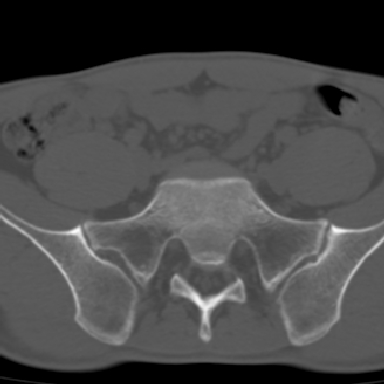

m 30 腰背部不适半年; 清晨时僵硬; 活动症状有所改善

双侧骶髂关节下2/3关节面模糊,毛糙,可见小囊状骨质破坏区.支持强直性脊柱炎.

强直性脊柱炎的早期改变!不仅表现为双侧骶髂关节,第5腰椎与骶椎间的关节突关节也有类似改变。

双侧骶髂关节下2/3关节面模糊,毛糙,髂骨侧可见小囊状骨质破坏区,骶髂关节间隙增宽(软骨破坏期)。支持早期强直性脊柱炎。

双侧骶髂关节下2/3关节面模糊、毛糙,可见小囊状骨质破坏区,呈虫咬状改变,周围可见增生硬化.支持强直性脊柱炎早期表现.